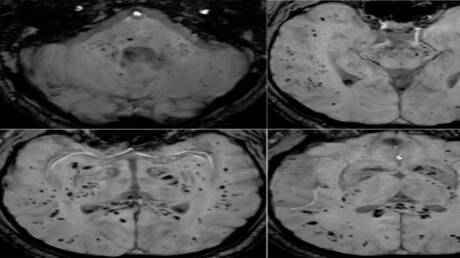

سرايا - أظهر تحليل صور بالرنين المغناطيسي أن فيروس كوفيد-19 يترك أثرا لا يُمحى في الدماغ، ويستمر تأثيره حتى بعد التعافي التام.

أظهرت دراسة حديثة أجراها علماء في جامعة غريفيث الأسترالية ونُشرت في مجلة Brain, Behavior, Immunity Health أن فيروس كوفيد-19 لا يؤثر على الجهاز التنفسي فحسب، بل يترك أثرا ملموسا على الدماغ، ويستمر تأثيره حتى لدى الأشخاص الذين يعتبرون أنفسهم متعافين تماما، حتى إذا لم تظهر عليهم أعراض واضحة.

وأوضح الباحث الرئيسي الدكتور كيران تاباليا أن الفريق استخدم طرق التصوير بالرنين المغناطيسي متعددة الوسائط لدراسة المادة الرمادية والبيضاء في الدماغ، وهي مهمة للذاكرة والوظائف الإدراكية والصحة العامة للدماغ. ووجد الباحثون اختلافات ملحوظة في أنسجة الدماغ وموادها الكيميائية العصبية وشدة الإشارة وبنية الأنسجة لدى المتعافين من كوفيد-19، حتى في حالات الإصابة التي اعتبرت بسيطة.